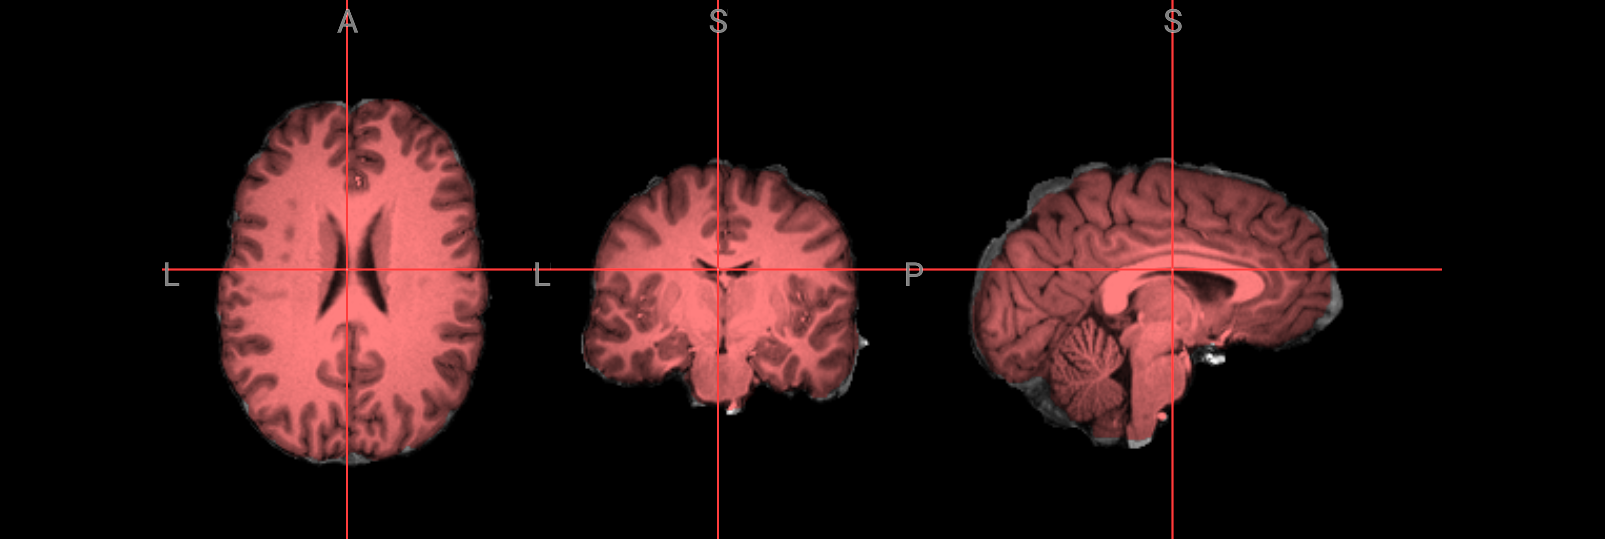

Fixing a bad skullstrip#

If the skullstripping results aren’t satisfactory, you can adjust the parameters in the bet

command. The -f

option sets the fractional intensity threshold, which controls how much brain tissue is included—lower values result in a more generous brain mask, while higher values are more conservative. If too much brain was removed, try lowering the threshold. For example:

!bet ./ds000102/sub-08/anat/sub-08_T1w.nii.gz ./FSL_preproc/sub-08_T1w_brain_f02.nii.gz -f 0.2

# Overlay brain extacted image with f=0.2 in red color ontop of the previous one with f=0.5 (gray)

nv = NiiVue()

nv.load_volumes([

{"path": "./FSL_preproc/sub-08_T1w_brain_f02.nii.gz", "colormap": "gray", "opacity": 1.0},

{"path": "./FSL_preproc/sub-08_T1w_brain.nii.gz", "colormap": "red", "opacity": 0.5},

])

nv

Image(url='https://raw.githubusercontent.com/NeuroDesk/example-notebooks/refs/heads/main/books/images/fsl_preproc_bet_02.png')